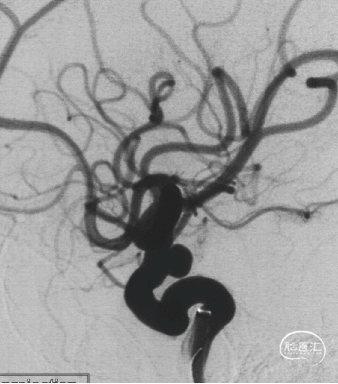

现病史:患者因头痛17天,外院行头颅CTA提示:左侧颈内动脉交通段动脉瘤,动脉瘤大小约5.3×5.4mm,形态不规则,左侧大脑前动脉A1段瘤样凸起。

初步诊断:左侧颈内动脉交通段动脉瘤。

可见一小泡自动脉瘤瘤体上发出

瘤体最大径6.92mm

远端血管直径:3.28mm

近端血管直径:3.98mm

同侧A1可见一小瘤突起